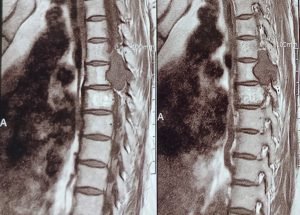

Expert spine services including minimally invasive surgery, pain management, and deformity correction.